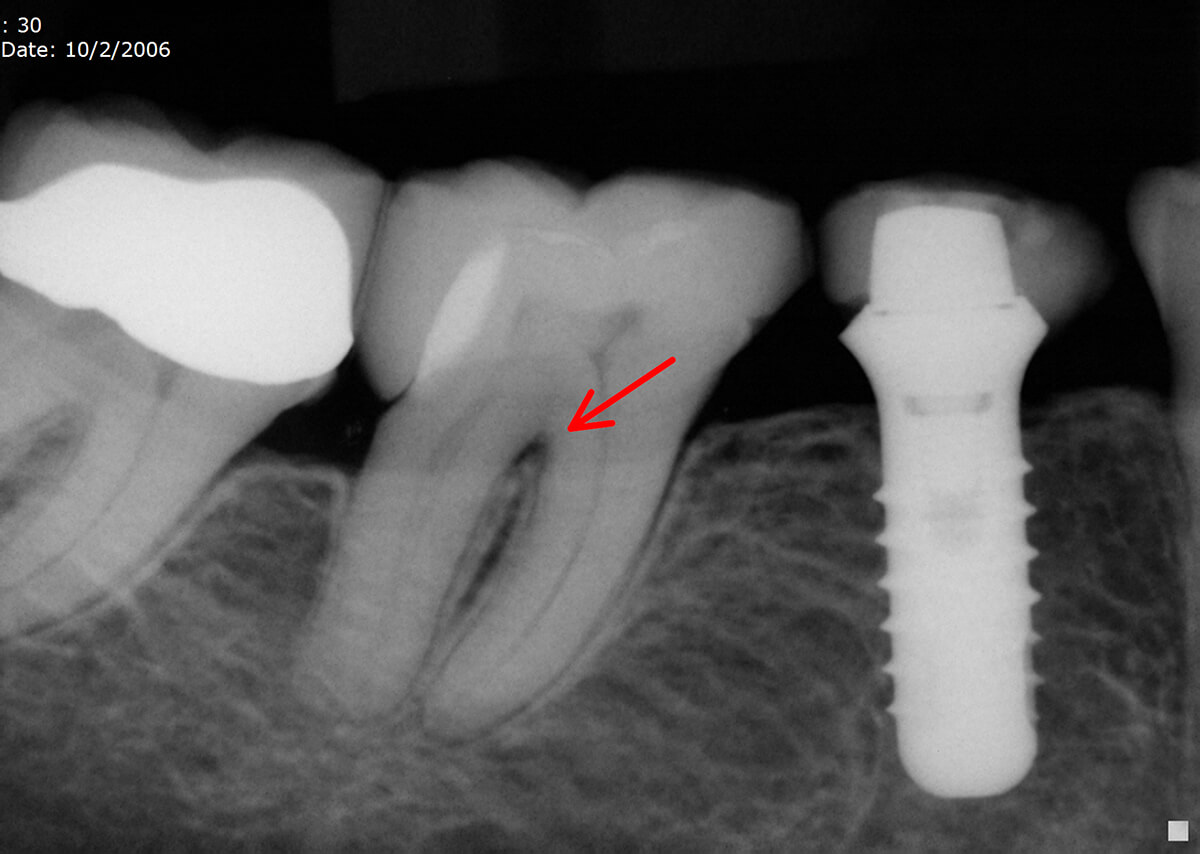

Lateral & Accessory Canals. SoCal Root Canal Accessory Canal Def ( 2007) defined an accessory canal as a fine branch of the pulp canal that diverged at an oblique angle from the main. Web accessory canals are secondary canals that emanate from the main canal and travel at an angle alongside it before exiting. Web accessory or nutrient canals are the canals other than the mandibular canal, running through the. Accessory Canal Def.

The Furcation Accessory Canal Case Studies Pure Dental Learning Accessory Canal Def Web accessory auricles (aas) were classified as pedunculated, sessile, areolar, remnant, and depressed. Web accessory or nutrient canals are the canals other than the mandibular canal, running through the buccal and/or lingual. Web endodontic terms (aae 2016), ‘an accessory canal is a branch of the main pulp canal or chamber that communicates with the. Web accessory canals are secondary canals. Accessory Canal Def.